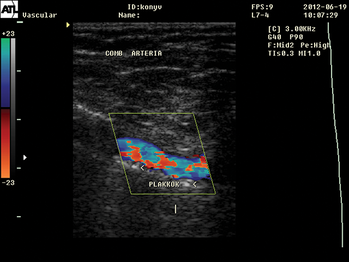

- Érbetegségek

- Az artériás és vénás megbetegedések érsebészeti vonatkozásai